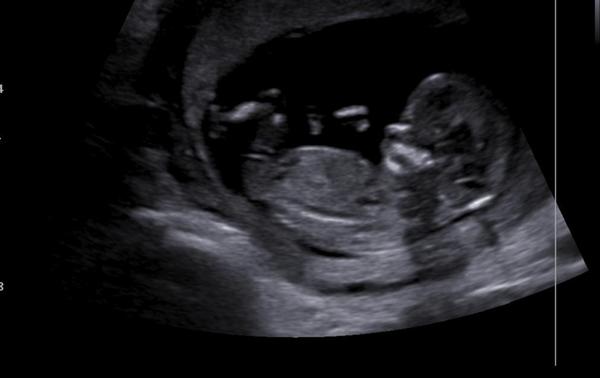

Ahoj všem 🙂 mám fotečku z ultrazvuku a zajímalo by mě pohlaví vůbec netuším 😃 asi jsem úplně blbá ale nějak se v té fotce nevyznám. Je to fotečka z 12+4. Co myslíte?

Jak píše @bodlinka24 mělo by se to poznat podle hrbolku jak je postavený k páteři. Takže nejspíš holka

@hanussenka Podle téhle fotky bych se klonila spis k holčičce, ale fotky často zkresluji... Je třeba sledovat ultrazvuk, jestli tam hrbolek směřuje nahoru (chlapeček), nebo jde rovnoběžně s páteří (většinou takové 2 čárky)=holcicka 🙂. Já jsem takhle syna ve 13.tt poznala a teď si myslím, ze to bude holka :D, ale potvrdí mi to v úterý, tak jsem zvedava, jestli jsem to zase uhodla... Jinak jak který dr... Někteří to říkat nechtějí, protože v některých případech se to urcit nedá, nebo je to sporné, ale pokud je zkušený, tak bud ví, nebo řekne, ze je to zkratka v “šedé zóně” a musíte počkat 🙂.

@andreajkab Je sice brzy, ale pri správném natočení a dobre fotecce se dá odhadnout, co se z toho vyvrbi. Zkušený lékař to dokáže urcit dokonce s téměř 90%jistotou. Ovšem tahle fotka je dost rozmazana a pohlavní hrbolek zakrývá nozicka :(...Takže asi nikdo neporadí... Neco jako hrbolek tam trcí, takže bych tipla holcicku, ale neni vidět cely a nejsem žádný odborník, takže to skutečně berte jen jako tip ;)